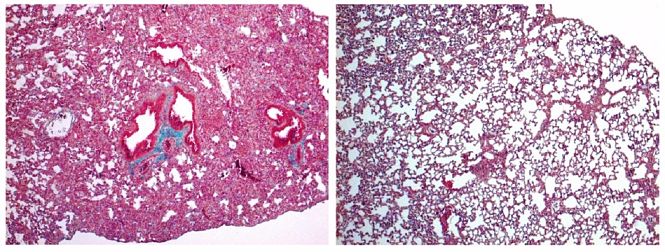

Los investigadores han evaluado la capacidad de la cortistatina para regular la fibrosis hepática usando dos modelos experimentales de hepatotoxidad y colestasis en ratones generados por exposición crónica a un agente tóxico y por ligadura de las vías biliares,

respectivamente.

"Encontramos que la expresión hepática de cortistatina se correlacionó inversamente con el grado de fibrosis hepática en ratones y humanos con trastornos hepáticos de distinta etiología. Los ratones deficientes en cortistatina mostraron signos exacerbados de daño hepático, fibrosis y cirrosis y mayores tasas de mortalidad cuando fueron expuestos a estímulos lesivos tóxicos y colestáticos. En comparación con los ratones con dotación genética normal del neuropéptido, las células hepáticas no parenquimatosas aisladas de ratones con deficiencia en cortistatina mostraron una mayor presencia de células con fenotipos de miofibroblastos activados", ha comentado el investigador, Mario Delgado.

En este sentido, añade que el tratamiento con cortistatina revirtió in vivo e in vitro estos fenotipos fibrogénicos exagerados y protegió de la progresión a fibrosis hepática grave en respuesta a la lesión hepática.